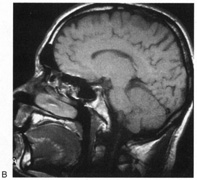

DISORDERS OF COLOR PROCESSING Cerebral Dyschromatopsia Cerebral (central) achromatopsia refers to complete loss of color perception, whereas cerebral dyschromatopsia indicates some residual color perception, as is most often the case. Both are rare. Hemiachromatopsia refers to color loss restricted to the contralateral hemifield,234,235 and may be more common but under-recognized. Achromatopsic patients generally are symptomatic, complaining that the world appears in shades of gray.236–239 Some also report that the world appears less bright240 or has a “dirty gray” tinge.241 Less frequently, patients report a tinge to the world, as if peering through a colored filter.242 Daily activities that use color discrimination are impaired, such as distinguishing coins, stamps, or traffic lights: A good account exists of the experience of an achromatopsic artist.243 Effects on “color constancy” are an important issue. The wavelengths reaching the eye from an object depend on both its reflectant properties and the light illuminating the scene. Yet, the color of objects remains stable under a wide range of environmental and lighting conditions.244,245 For instance, an apple continues to look red in sunlight, incandescent light, and fluorescent light, in an orchard or a grocery display. This ability to “discount the illuminant” depends on neural computations in retina and cortex.244 These computations likely average the spectral luminance over large regions of the surrounding background to deduce the nature of the illuminant, and this information is then taken into account to derive the true color of any object in the scene.244,246 A defect in color constancy should result in color percepts that vary with changes in illumination. Patients with achromatopsia have a more severe deficit, in that they lack any color percept at all. Testing such patients for constancy of something they do not perceive is paradoxical, but this can be done on dyschromatopsic patients, who have some residual hue sensitivity. Some studies have shown that color constancy is impaired in these patients.247–250 These patients all had bilateral lingual and fusiform gyral lesions, except for one unilateral case.248 Not all color perception is lost in achromatopsia. Some color input from the cones and retinal ganglion cells of the parvocellular pathway still can be processed. Thus, both trichromacy and color opponency have been shown in photopic spectral sensitivity curves247,251,252 and evoked potential or psychophysical measures of chromatic contrast sensitivity.252,253 Likewise, performance with anomaloscope testing can resemble an anomalous trichromat rather than a monochromat, despite the experience of the world as monochromatic “shades of gray.”254 Achromatopsics can use color-opponent signals to locate chromatic boundaries, even though they cannot perceive the colors that determine those boundaries. Thus achromatopsics can detect the movement of chromatic stimuli,255,256 even performing at normal levels with suprathreshold chromatic contrast.257 This indicates that wavelength variation is still perceived, even if color is not. Achromatopsia is seldom an isolated finding. Most commonly it forms one component of a tetrad that includes superior quadrantanopia, prosopagnosia, and topographagnosia. Superior field loss is almost always present, because the ventral occipito-temporal lesion that causes achromatopsia frequently extends into the inferior calcarine cortex or optic radiation. Similarly, only a few cases without prosopagnosia have been reported.258 Experimental testing has revealed in some patients a problem with detecting stimuli with low salience,259 which has also been described in monkeys with V4 lesions, and thought to indicate inefficient attentional allocation in form processing. Other occasionally associated defects include visual object agnosia,251,260 alexia in achromatopsic patients with right hemianopia,238,258 and amnesia with additional ventral temporal lobe damage.238,260 Achromatopsia is caused by lesions of the lingual and fusiform gyri,245,261 as confirmed by modern imaging.240,241,251,254,258,262 Lesions of the middle third of the lingual gyrus or white matter behind the posterior tip of the lateral ventricle may be critical.240,263 Bilateral lesions are necessary for complete achromatopsia. In monkeys, color-selective responses are found in area V4.245 However, lesions of V4 do not impair hue perception significantly.264–269 Rather, defects in chromatic perception require extensive bilateral lesions, including areas TE and TEO.270,271 In humans, functional imaging reveals several areas involved in color processing, notably a V4 homologue and a second area named V4 alpha or V8 in the fusiform gyrus,272,273 as well as other more distant regions.274–276 Thus color processing involves a network of regions, and it is probable that a severe achromatopsic defect may require damage to or disconnection of several components of the network, rather than just a lesion of a single region like the human V4 homologue.267,277,278 Achromatopsia is most often caused by strokes. Bilateral sequential or simultaneous infarctions in the territories of both posterior cerebral arteries can occur, or multiple infarcts may result from a coagulopathy.279 Achromatopsia may be the first symptom of a stroke or the outcome of an initial cortical blindness. Other bilateral lesions causing achromatopsia include herpes simplex encephalitis,251 cerebral metastases,258 repeated focal seizures,280 focal dementia,281 and even migraine aura, causing a transient achromatopsia.282 Temporo-occipital white matter damage has caused a reversible dyschromatopsia in one patient with carbon monoxide poisoning,283 a condition that usually causes an apperceptive agnosia with spared color perception.245 HEMIACHROMATOPSIA. Achromatopsia in the contralateral hemifield alone can follow unilateral right or left occipital lesions (Fig. 18). Patients are typically asymptomatic until the defect is demonstrated on examination.234,235 Hemiachromatopsia is usually associated with a superior quadrantanopia;234,235,241 therefore, the color defect is only demonstrable in the remaining inferior quadrant. The preserved color vision in the ipsilateral hemifield allows normal or near-normal performance on centrally viewed tests of color vision such as pseudoisochromatic plates. The incidence of hemiachromatopsia is probably underestimated, given its asymptomatic nature and the failure of routine clinical color tests to detect its presence.